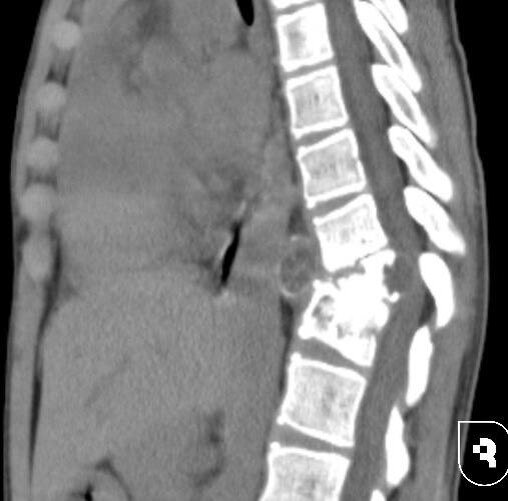

12-летнего мальчика доставили в Саратовский НИИ травматологии и ортопедии с сильными болями в спине, которые усиливались при ходьбе.

Обследование показало, что причиной симптомов стал компрессионный перелом десятого грудного позвонка, вызванный редким паразитарным заболеванием — эхинококкозом.

После подтверждения диагноза и исключения поражения других органов, врачи приняли решение о сложнейшей трехэтапной операции. Перед этим мальчику назначили терапию для борьбы с паразитами. На первом этапе медики выполнили левостороннюю торакотомию, удалили эхинококковую кисту и частично два позвонка. Затем исправили деформацию позвоночника с помощью специальной системы, после чего провели вторую операцию на грудной клетке и установили протез позвонка.

Во время хирургического вмешательства были обнаружены многочисленные эхинококковые кисты разного размера. Все доступные удалили, а крупные — пунктировали, чтобы избавиться от их содержимого.